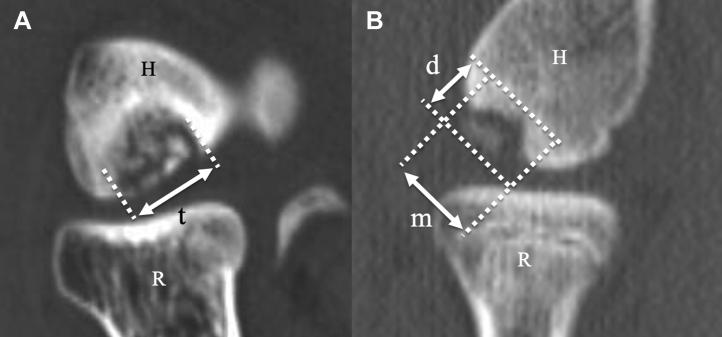

There were 26 and 6 patients in Groups A and B, respectively. Two patients did not obtain complete union. Clinical outcomes improved after the procedure. In univariate analysis, delayed union was associated with larger major diameter ( = .0004) and more depth ( = .03) of the osteochondral fragment measured by computed tomography, the presence of osteosclerosis in the subchondral bed on X-ray imaging ( = .003), and the presence of comminution of subchondral bone on ultrasound imaging ( = .01). In multivariate analysis, there was a significant difference only in the major diameter of the osteochondral fragment ( = .03). Receiver operating characteristic curves analysis shows that if the major diameter of the osteochondral fragment is 11 mm or less, 85% of patients achieve complete union of the osteochondral fragments within 6 months.

A组和B组分别有26例和6例患者。2例患者未实现完全愈合。术后临床结果有所改善。单因素分析显示,延迟愈合与计算机断层扫描测量的骨软骨碎片较大的长径(P = 0.0004)和更深的深度(P = 0.03)、X线成像显示的软骨下骨硬化(P = 0.003)以及超声成像显示的软骨下骨粉碎(P = 0.01)有关。多因素分析显示,仅骨软骨碎片的长径存在显著差异(P = 0.03)。受试者工作特征曲线分析表明,如果骨软骨碎片的长径为11 mm或更小,85%的患者可在6个月内实现骨软骨碎片的完全愈合。